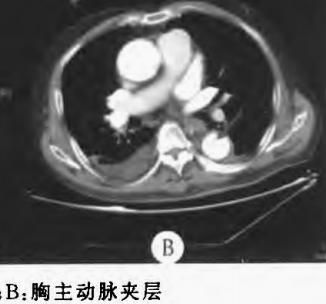

增强CT一看,主动脉夹层,密度相对高的是流动的血液!

下图的胸部CT平扫,基本上大约肯定可以看到一条线样阴影,将主动脉一分为二!

增强CT一看,主动脉裂开了!